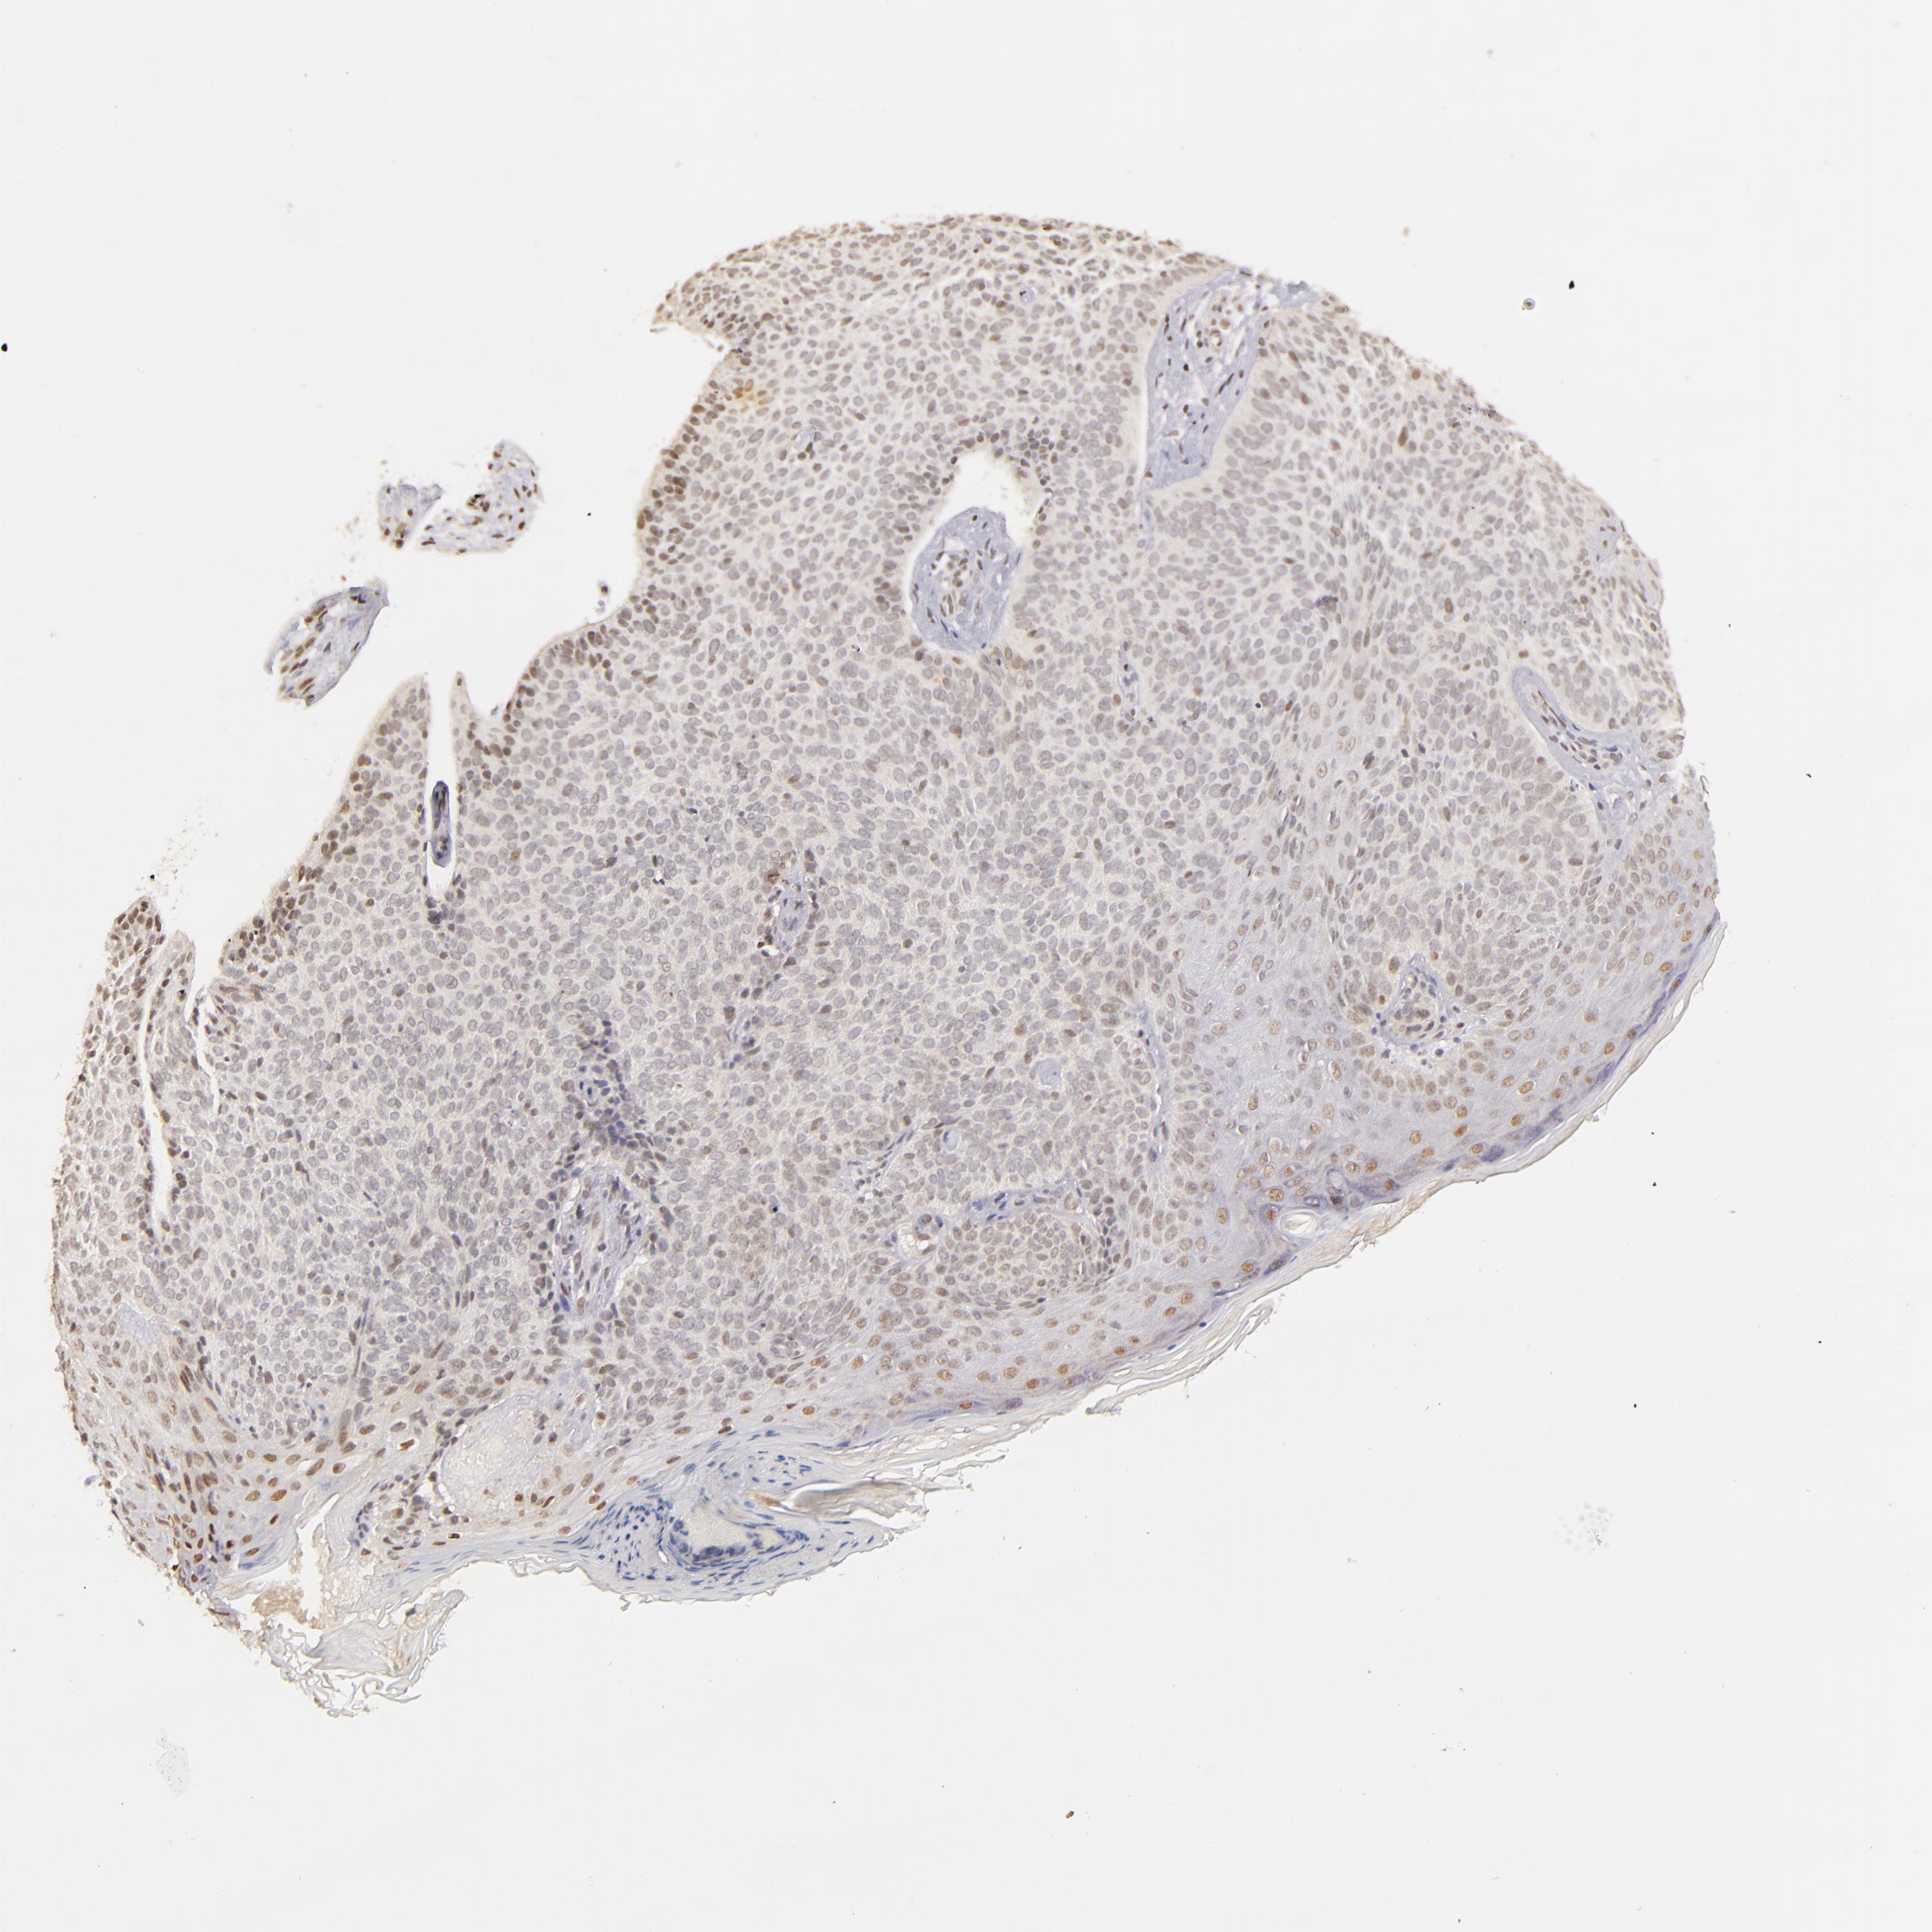

SKIN CANCER - Protein expressioni

A mouse-over function shows sample information and annotation data. Click on an image to view it in a full screen mode. Samples can be filtered based on level of antibody staining by selecting one or several of the following categories: high, medium, low and not detected. The assay and annotation is described here.

Antibody stainingi

Antibody staining in the annotated cell types in the current human tissue is reported as not detected, low, medium, or high, based on conventional immunohistochemistry profiling in selected tissues. This score is based on the combination of the staining intensity and fraction of stained cells.

Each image is clickable and will lead to virtual microscopy that enables deeper exploration of all samples and also displays staining intensity scores, fraction scores and subcellular localization as well as patient and tissue information for each sample.

Antibody HPA004174

Antibody CAB002617

Staining

High

Medium

Low

Not detected

Intensity

Strong

Moderate

Weak

Negative

Quantity

>75%

75%-25%

<25%

None

Location

Nuclear

Cytoplasmic/membranous

Cytoplasmic/membranous,nuclear

Basal cell carcinoma

Squamous cell carcinoma, NOS